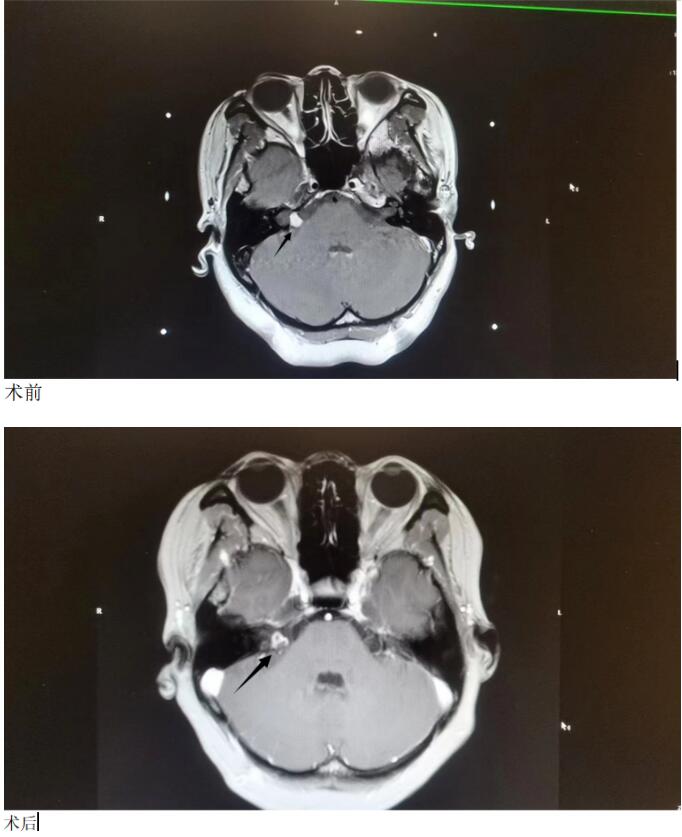

临床案例:

患者,女,42岁,缘于半年前出现右侧听力下降,未予重视;近一月加重,于当以医院行颅脑CT检查示:右侧小脑脑桥角占位性病变。2023年3月,为求进一步治疗,来到首都医科大学三博脑科医院福建院区伽玛刀中心进行伽玛刀治疗,10月复查,听神经瘤明显缩小,坏死。